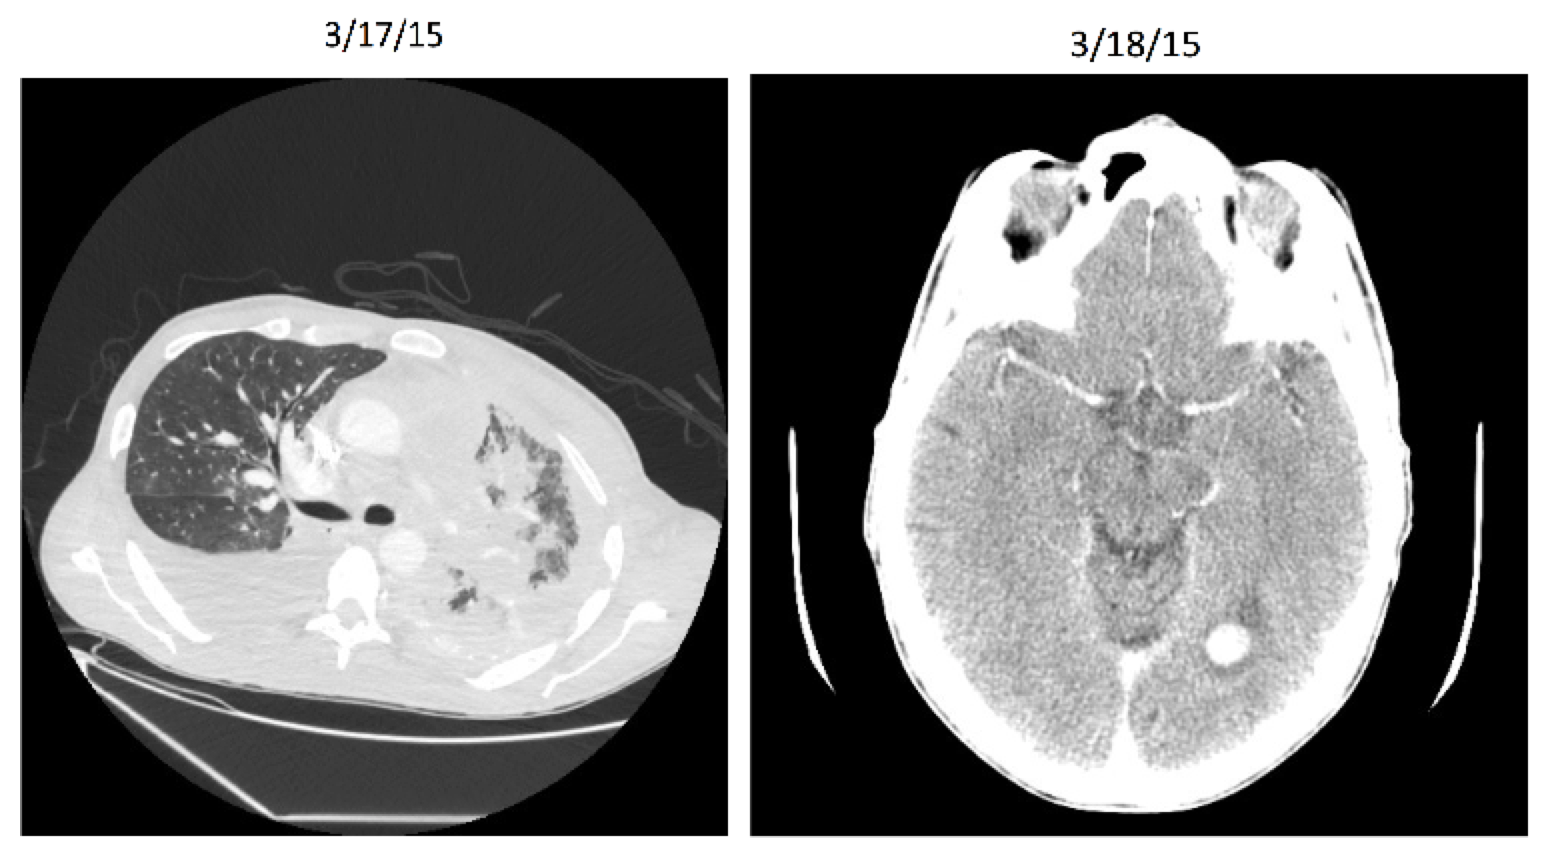

Entrectinib: Patient X Before

Entrectinib: Patient X After

Entrectinib

Targeted therapy (NTRK gene rearrangement)

Very stringent inclusion/exclusion criteria

Effective for other histologies (including breast, colorectal, and neuroblastoma)

8/11 responders for lung cancer in initial study